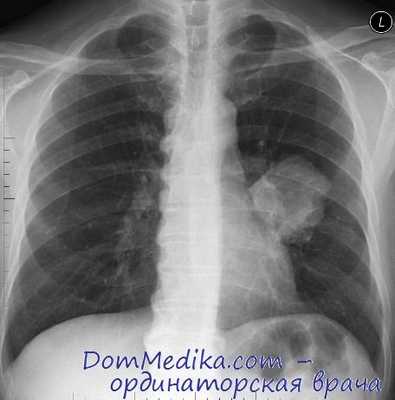

Выраженные физикальные проявления на ранних этапах онкопроцесса в легких нехарактерны. Основным источником выявления злокачественных опухолей легких на стадии отсутствия клиники является рентгенография. Злокачественные опухоли легких могут быть случайно выявлены при проведении профилактической флюорографии. При рентгенографии легких определяются опухоли диаметром более 5-6 мм, участки сужения и неровностей контуров бронхов, ателектаза и инфильтрации. В сложных диагностических случаях дополнительно проводят МРТ или КТ легких.

КТ ОГК. Солидная мягкотканная опухоль в верхней доле левого легкого с морфологическими признаками злокачественности.